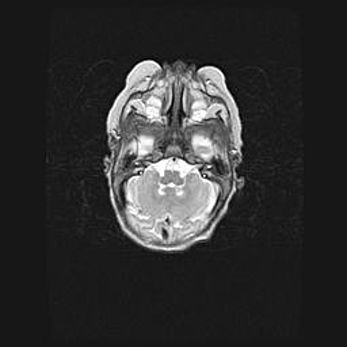

Подострая гематома правой гемисферы мозжечка.

Наружная гидроцефалия.

Возраст: 15 дней

Вес: 3100 г

Пол: женский

Окружность головы: 37 см

Срок гестации: 35-36 недель

При открытой наружной форме гидроцефалии у новорожденных расширяются и переполняются субарахноидные пространства.

Кровоизлияния в мозжечок имеют две клинико-анатомические формы: полушарные гематомы и кровоизлияния в червь.

К появлению этой патологии может привести: повреждения головного мозга, возникающие в результате асфиксии и гипоксии плода при беременности, или травмы во время родов. Редко гематома мозжечка может быть результатом первичной коагулопатии и сосудистой мальформации, диссеминированном внутрисосудистом свертывании, изоиммунной тромбоцитопении.